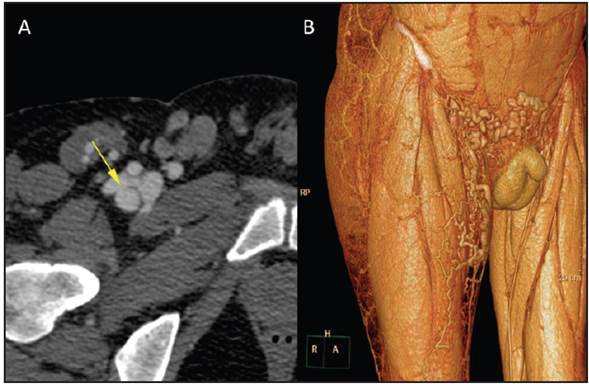

This was a 42-year-old male who underwent surgery for transposition of the great arteries as a child. Twenty years later a catheterization through the right deep femoral artery was performed. Over the last five years he has had edema with a change in color of his right foot 50 seconds after going from a lying to a standing position (Figure 1). Computed tomography angiography corroborated the diagnosis of an arteriovenous fistula (AVF) in the right femoral system (Figures 2 and 3). He was referred to vas cular surgery for stent placement.